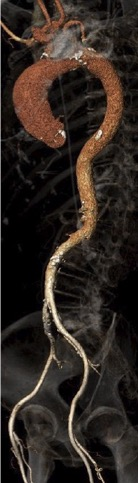

升主动脉扩张,升主最宽处44.9mm。

腹主-双侧髂总动脉未见明显钙化,股-髂动脉走行流畅、内径可,分叉高。

升主动脉最宽处44.9mm

弓部宽度角度尚可

股-髂动脉走行、内径可